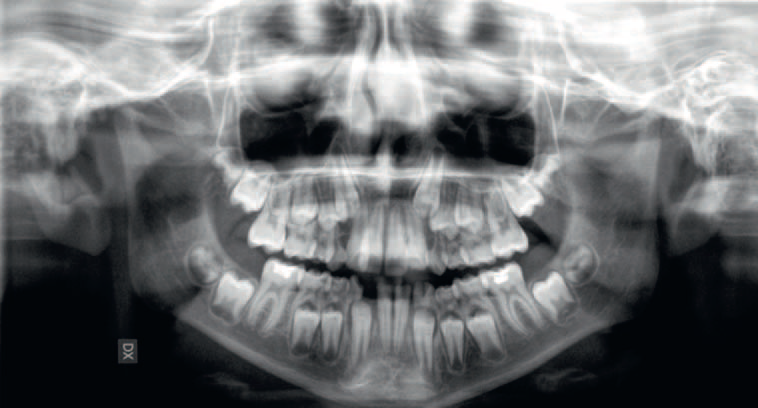

Streszczenie: W pracy przedstawiono postępowanie kliniczne u pacjentki z obustronnym wrodzonym brakiem siekaczy żuchwy. Ten stan jest stosunkowo rzadki i zawsze wymaga dokładnego rozpoznania i planowania leczenia. Wybrana dla pacjentki strategia leczenia obejmowała zamknięcie przestrzeni poprzez protrakcję tylnych zębów żuchwy i zastąpienie brakujących siekaczy kłami. Ponadto omówiono problemy wynikające z takiego planu leczenia, takie jak okluzja chroniona przedtrzonowcami i rozbieżność wielkości zębów. W oparciu o przypadek przedstawiony w niniejszej pracy można wnioskować, że zamknięcie przestrzeni można uznać za skuteczne podejście terapeutyczne, pozwalające na uzyskanie zadowalających wyników funkcjonalnych i estetycznych.

Hipodoncja jest definiowana jako wrodzony brak jednego lub kilku zębów [1]. Cięższymi postaciami agenezji zębów są oligodoncja i anodoncja, charakteryzujące się odpowiednio brakiem więcej niż sześciu zębów i całkowitym brakiem zębów. Są one zwykle związane z innymi schorzeniami ogólnoustrojowymi, takimi jak: zespół Downa, dysplazja ektodermalna i zespół Ellisavan Crevelda [1, 2]. Istnieją cztery główne teorie dotyczące etiologii agenezji zębów; może być ona traktowana jako manifestacja trendu ewolucyjnego lub może być spowodowana czynnikami środowiskowymi albo ogólnoustrojowymi, takimi jak: uraz, stan zapalny, zakażenia kości szczęki/żuchwy czy też zaburzenia hormonalne [...]